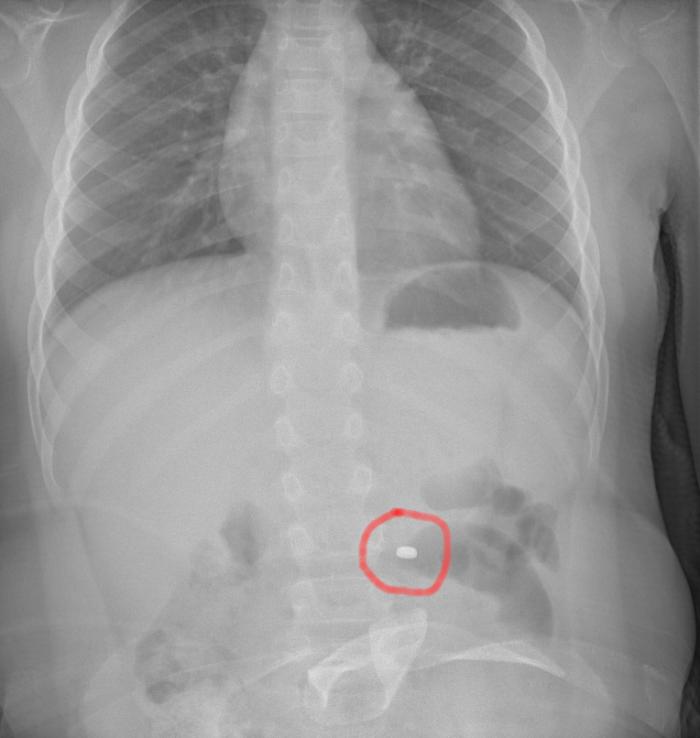

Bimbo operato al Cannizzaro dopo aver ingerito una pila a bottone

La famiglia, naturalmente spaventata, dopo una prima valutazione al pronto soccorso della propria città, è stata indirizzata al Cannizzaro. Qui i medici hanno compreso il pericolo e applicato le linee guida riferite precisamente all’ingestione di una pila a bottone. Eseguita la radiografia dell’addome che ha messo in evidenza la presenza e la localizzazione del corpo estraneo, il bambino è stato condotto in sala operatoria dove gli endoscopisti, con l’assistenza degli anestesisti, hanno potuto estrarre in sicurezza l’oggetto, prima che esso potesse causare conseguenze più importanti. Dopo una notte in osservazione, tornato in piena salute, il bimbo ha fatto rientro a casa con i genitori.